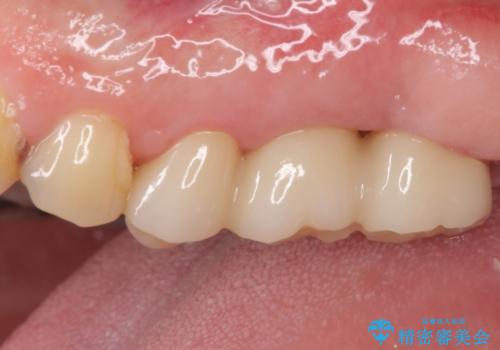

極力抜歯が回避する方法を選択して診察を開始しましたが、1本は保存困難と判断されたため、フルジルコニアブリッジによる補綴治療を行うこととしました。

抜歯をしたことで違和感はなくなり、ブリッジを装着したことでしっかりと噛めるようになり、患者様には大変満足していただきました。